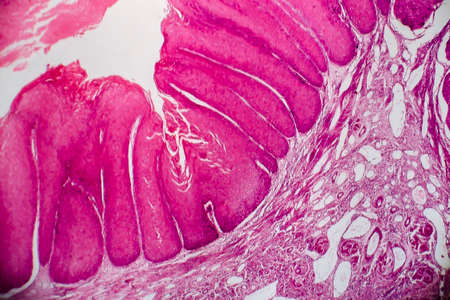

Condyloma acuminatum, also known as genital warts. Light micrograph, photo under microscope

Condyloma acuminatum, also known as genital warts. Light micrograph, photo under microscope